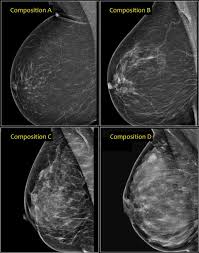

What Is A Mammogram Cdc

What Is A Mammogram Cdc from www.cdc.gov